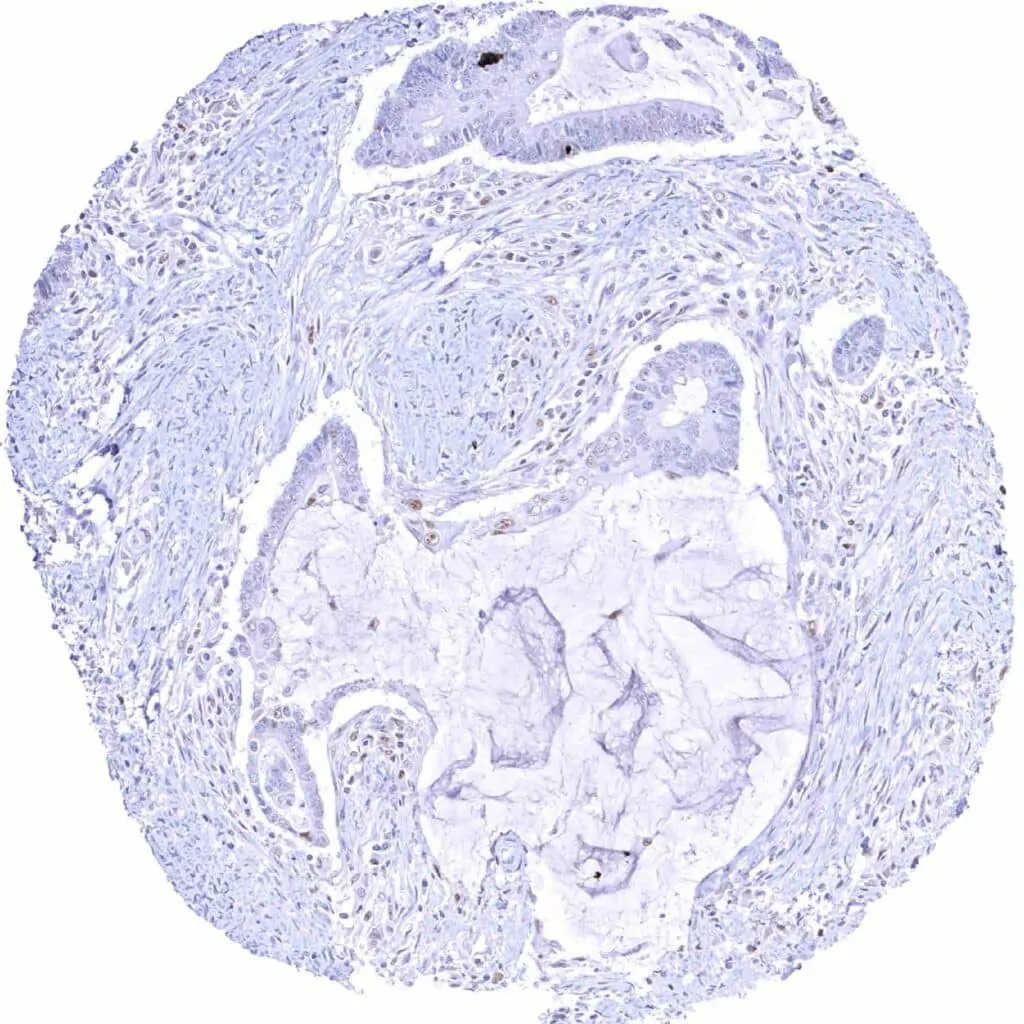

Esophagus – Squamous cell carcinoma with weak to moderate Cyclin E1 staining of tumor cells